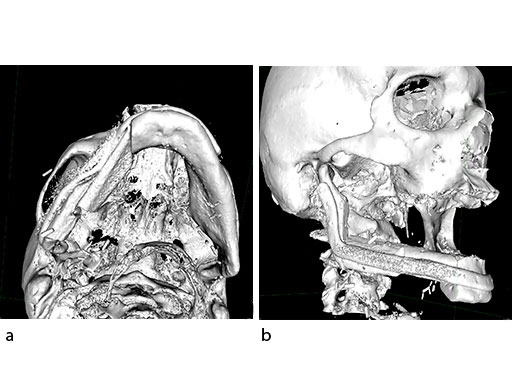

A 58-year-old male patient had oral cancer (T4n0m0) infiltrating the alveolar process and the anterior border of the ascending ramus (Fig 2). The treatment plan involved resection, bilateral neck dissection (levels I to III), and primary mandibular reconstruction with a right osteomyofasciocutaneous fibula flap.

The design of the bony segments and the overall framework is defined in an interactive planning session between the surgeon and a medical engineer. In oncologic surgery, a primary reconstruction is preceded by a virtual tumor resection for exact matching of the defect and the bony restoration. In secondary reconstruction, it will often be necessary to reposition collapsed bony remnants and to level their cut edges in order to define the real extent of the preexisting defect. Patient specific plates for the mandible have the versatility to bridge almost all defect patterns in the mandible (Fig 1abc). After exarticulation of a condyle, they are even compatible with the Matrix Mandible condylar head add-ons as a joint component for temporary replacement. The cutting guides, templates, and the patient specific mandibular reconstruction plates can be supplemented with stereolithographic (STL) models of the mandible, displaying the defect and the composed fibular segments as either a hybrid or as separate items. In the separate format, the models are an ideal instrument for double-checking. The defect size and the correct placement of the patient specific plates for the mandible are controlled by inserting the STL fibular segment assembly in situ. On a side table, the fitting of the real fibular segments into the defect of the STL model can be assessed.

At this stage, future dental implant insertion requires an alveolar process in a lingual shift position. To this end, the anterior segment is aligned with a medial offset. The posterior segment, which replaces the angle/anterior ramus region, is arranged with an overlapping zone. The inner cortex of the posterior segment in the area of intersection is trimmed to keep the restoration within the bounds of the original width of the angle. This results in a sort of "bayonet connection". The basal border of the mandibular body is not built up, since it is not functionally relevant.